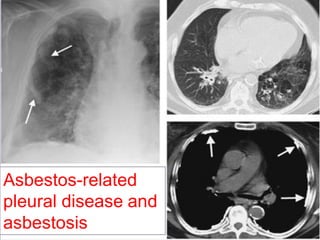

Asbestos-related

pleural disease and

asbestosis

Rule no. 5

Associated pleural thickening and/or

calcification suggest asbestosis.